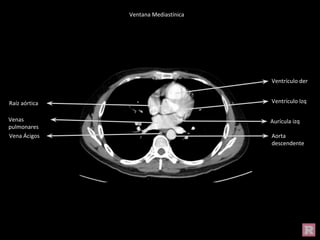

Aorta ascendente

Tronco pulmonar

V. cava superior

Aorta

descendente

A. pulmonar izq

V. Ácigos

Ventana Mediastínica